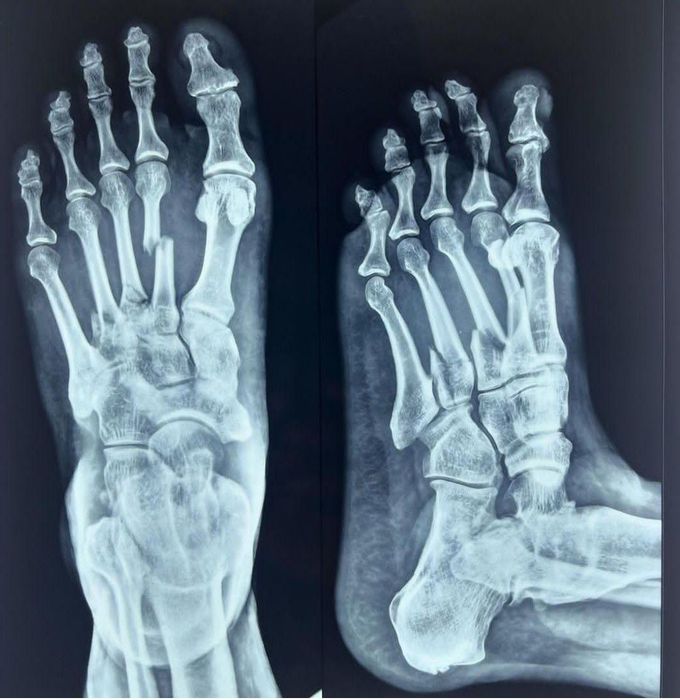

Identify the Pathology in the x-ray above.

This is a trauma case w/ multiple fractures both posterior & lateral of the bridge & instep w/ multiple tore ligaments & likely 95% past medical history of arthritis and benign bone neoplasm of bilateral sesamoid bones.